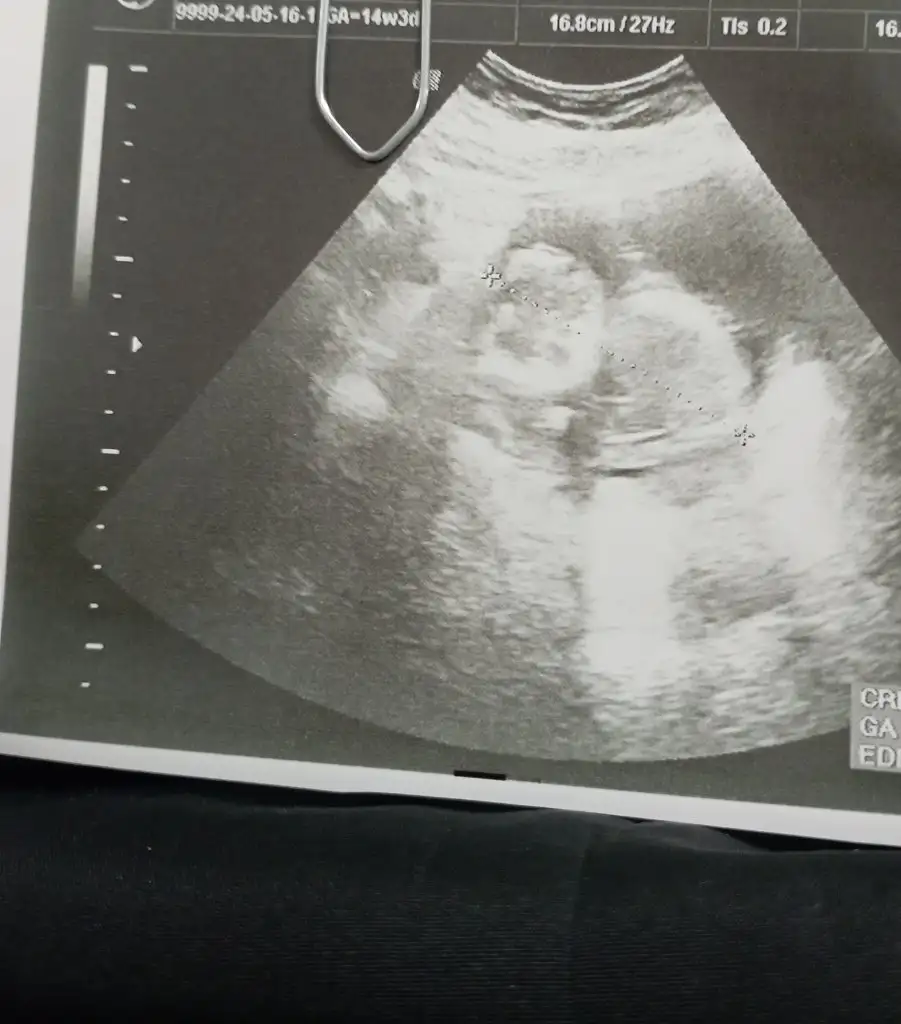

Kizlaaaat bizede tahminde bulunur musunuz doktor ilk kız dedi sonra çıkıntı görüyorum erkek dedi

yaa bende şuan 20.haftadayım 13.haftada kız dedi doktorum 15 ve 16 da da erkeğe benziyor ama kordon da olabilir dedi organ taramada netleşir dedi salı günü gideceğiz ona da insan merak ediyor tabi